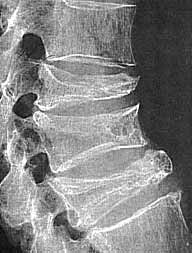

Die Demineralisierung des Skeletts, und somit die Abnahme der Knochenmasse (Osteoporose), tritt ab einem Alter von etwa 50 Jahren auf. Frauen sind (hormonell bedingt) häufiger betroffen als Männer. Man beachte, dass vor allem die horizontalen Knochenbälkchen verschwunden sind. |

Dies führt zu einer Demineralisierung der Knochen. Diese werden brüchiger und es kommt vor, dass Patienten schon beim Husten oder Niesen Rippen brechen. Weitere bevorzugte Stellen für solche Knochenbrüche sind Wirbelkörper (Kompressionsfrakturen), der Oberschenkelhals und die Unterarme.

Links : Osteoporose der Wirbelsäule mit diversen Kompressionsfrakturen.